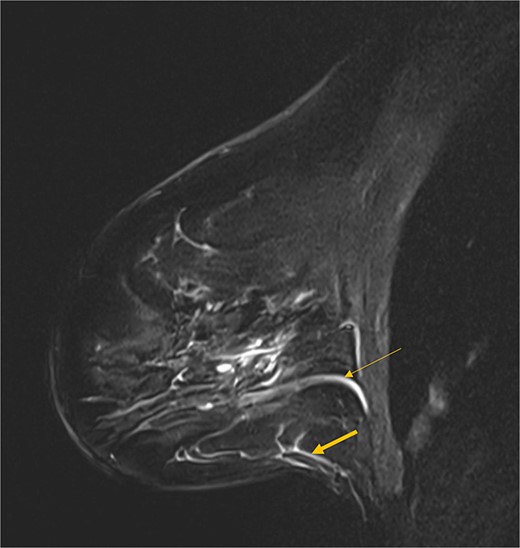

Vascularity is particularly important when accounting for the subsequent tissue folding to create the new breast mound [10]. Recent discoveries regarding the fifth anterior intercostal artery perforator (AICAP) vessels explain how such a large area of tissue remains perfused following a Goldilocks mastectomy [15]. Described by Nahabedian et al., it is now understood that instead of running with the fourth AICAP vessels in the mammary septum as previously thought, the fifth AICAPs take a divergent course and travel within the subcutaneous fat at the 6 o’clock position (Fig. 3). By performing an anatomical mastectomy and preserving the anterior lamellar fat of the breast, these vessels are retained and are the primary blood supply to the new breast mound [15].

Sagittal MRI image showing the fourth AICAP vessels in the breast septum (thin arrow) and the fifth AICAP vessels travelling in the subcutaneous tissue (thick arrow).